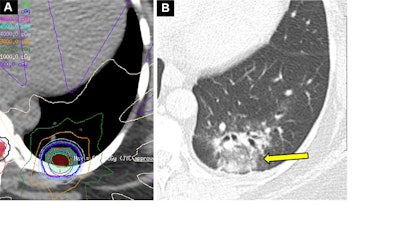

Acute radiation-induced pneumonitis after SBRT (65 Gy, four fractions) in a 53-year-old woman with leiomyosarcoma of the uterus with a left lower lobe metastasis manifesting as a small nodule (not shown). (A) Axial dosimetric reconstruction of a CT image obtained for SBRT planning shows the metastasis receiving the maximal isodose (6500 cGy). (B) Axial CT image obtained 12 months after completion of RT shows focal ground-glass and consolidative opacities confined to the treatment plan (arrow). Note that acute lung injury with SBRT typically manifests later than with conventional RT (i.e., >12 weeks after completion of therapy), and in 25% of patients, the first CT manifestations occur more than one year after completion of RT.Acute radiation-induced pneumonitis after SBRT (65 Gy, four fractions) in a 53-year-old woman with leiomyosarcoma of the uterus with a left lower lobe metastasis manifesting as a small nodule (not shown). (A) Axial dosimetric reconstruction of a CT image obtained for SBRT planning shows the metastasis receiving the maximal isodose (6500 cGy). (B) Axial CT image obtained 12 months after completion of RT shows focal ground-glass and consolidative opacities confined to the treatment plan (arrow). Note that acute lung injury with SBRT typically manifests later than with conventional RT (i.e., >12 weeks after completion of therapy), and in 25% of patients, the first CT manifestations occur more than one year after completion of RT.RadioGraphics